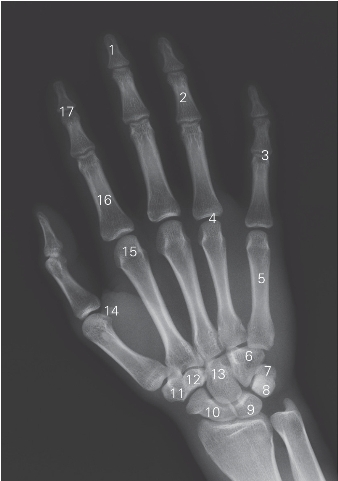

图7-4 手腕正位DR平片

1 远节指骨 distal phalanx 2 中节指骨 middle phalanx

3 近侧指间关节 proximal interphalangeal joint

4 掌指关节 metacarpophalangeal joint 5 第5掌骨 5th metacarpal bone

6 钩骨 hamate bone 7 豌豆骨 pisiform bone

8 三角骨 triquetrar bone 9 月骨 lunate bone

10 舟骨 scaphoid bone 11 大多角骨 trapezium bone

12 小多角骨 trapezoid bone 13 头状骨 capitate bone

14 籽骨 sesamoid bone

15 第2掌骨头 head of 2nd metacarpal bone

16 近节指骨 proximal phalanx

17 远侧指间关节 distal interphalangeal joint